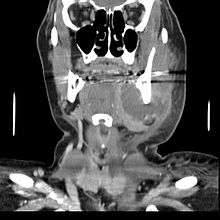

Complications

If left untreated, a severe tooth abscess may become large enough to perforate bone and extend into the soft tissue eventually becoming osteomyelitis and cellulitis respectively. From there it follows the path of least resistance and may spread either internally or externally. The path of the infection is influenced by such things as the location of the infected tooth and the thickness of the bone, muscle and fascia attachments.

External drainage may begin as a boil which bursts allowing pus drainage from the abscess, intraorally (usually through the gum) or extraorally. Chronic drainage will allow an epithelial lining to form in this communication to form a pus draining canal (fistula). Sometimes this type of drainage will immediately relieve some of the painful symptoms associated with the pressure.

Internal drainage is of more concern as growing infection makes space within the tissues surrounding the infection. Severe complications requiring immediate hospitalization include Ludwig's angina, which is a combination of growing infection and cellulitis which closes the airway space causing suffocation in extreme cases. Also infection can spread down the tissue spaces to the mediastinum which has significant consequences on the vital organs such as the heart. Another complication, usually from upper teeth, is a risk of septicaemia (infection of the blood) from connecting into blood vessels, brain abscess (extremely rare), or meningitis (also rare).